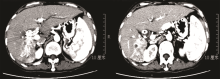

李勇:总体来说, PTCD的普适性较好, 若ERCP失败后仍可选择行PTCD治疗。因此针对该患者我们选择的是先行PTCD处理治疗。从图2的患者术中胆道造影图像可见:左肝内胆管扩张, 呈藤蔓状改变, 右肝胆管、胆总管未见造影剂充盈。左右肝管汇合区及胆总管上段见巨大充盈缺损, 相对应胆管不规则扩张, 少许造影剂可进入十二指肠。根据患者病例特点及影像学资料, 可诊断为局部肿瘤复发合并胆道癌栓形成。